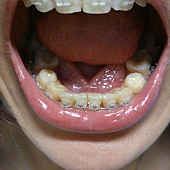

下排已經從內凹變成完全的圓弧型了,

速度真的很快,

目前側邊拔牙的牙縫還是挺大的

畢竟牙齒是一顆一顆在移動的,

橡皮筋的拉力主要是用最後面大臼齒的力量在拉犬齒,

所以這顆牙齒移動的很快,